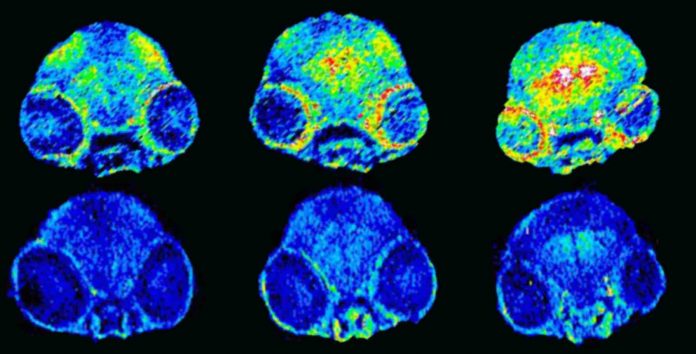

The molecule extracts the copper trapped in amyloid plaques, and reintroduces it in the brain’s normal enzymatic circuit (which needs copper to function). Administered orally to an Alzheimer’s mouse model, this molecule inhibits memory loss among sick mice.